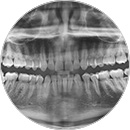

Ortopantomografía

Radiografía panorámica que muestra la totalidad de las estructuras orales.